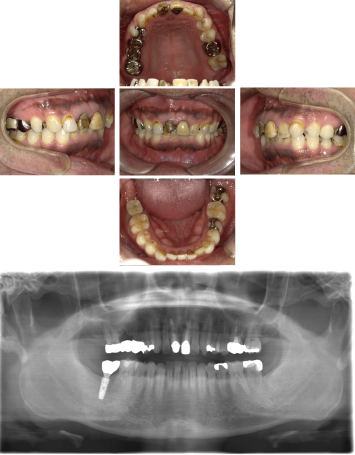

50代 女性 インプラント治療(GBR・ソケットリフト)

| 年代・性別 | 50代・女性 |

| 主訴 | Brの歯が取れそうなため、インプラントに変えたい。 |

| 部位 | 左下567 左上④5⑥ 右上67 |

| 治療期間 | 約3年9ヶ月 |

| 費用 | ¥3,224,500(税込) |

| 副作用・リスク |